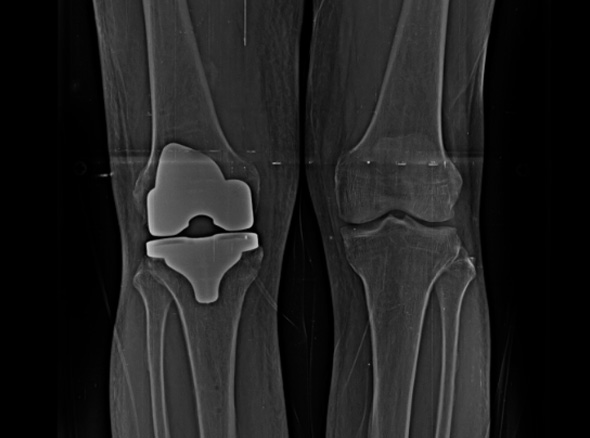

손상된 무릎 뼈를 제거하고, 그 부위에 특수 소재의 금속 재질로 구성된 인공관절을 삽입하는 수술을 시행할 수 있습니다.

관절연골이 망가져 쓸 수 없을 때 관절기능 회복을 위해 시행하며, 인공관절의 수명은 20~30년 정도 됩니다.

인공관절수술은 이러한 환자분들을 대상으로 시행하는 수술로

정밀검진 및 검사를 통해 관절 손상정도를 면밀히 파악하고 꼭 필요한 경우에만 수술을 진행합니다.

세계적인 의료기기 기업 스트라이커(Stryker)사의 특화된 임플란트를 사용합니다.

정밀한 설계, 내구성, 생체 적합성 등의 장점을 두루 갖추어 전 세계적으로 가장 많이 사용되고 있습니다.

말기의 퇴행성 관절염 환자에게 인공관절 수술은 최후의 수단으로 시행됩니다.

최대한 가볍고 오래 사용 가능하며 알러지를 거의 유발하지 않는 인공관절을 사용합니다.